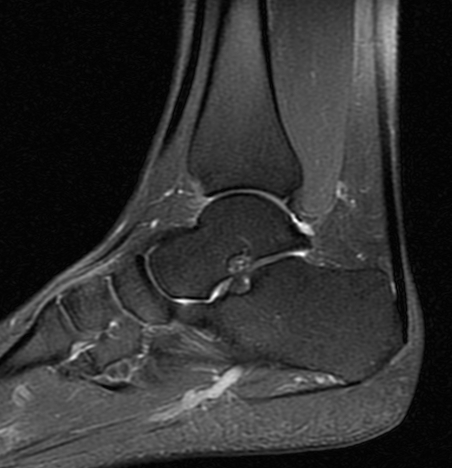

La durée de l’examen est variable selon la zone anatomique étudiée allant de 10 minutes (IRM cérébrale, IRM du genou, IRM d’épaule, IRM du poignet, IRM de la cheville, IRM cervicale, IRM lombaire …) à 25 minutes (IRM médullaire, IRM hépatique, IRM pancréatique, IRM rénale, IRM pelvienne, IRM de prostate…). Elle dépend également de la nécessité ou non d’injecter un produit de contraste (gadolinium).